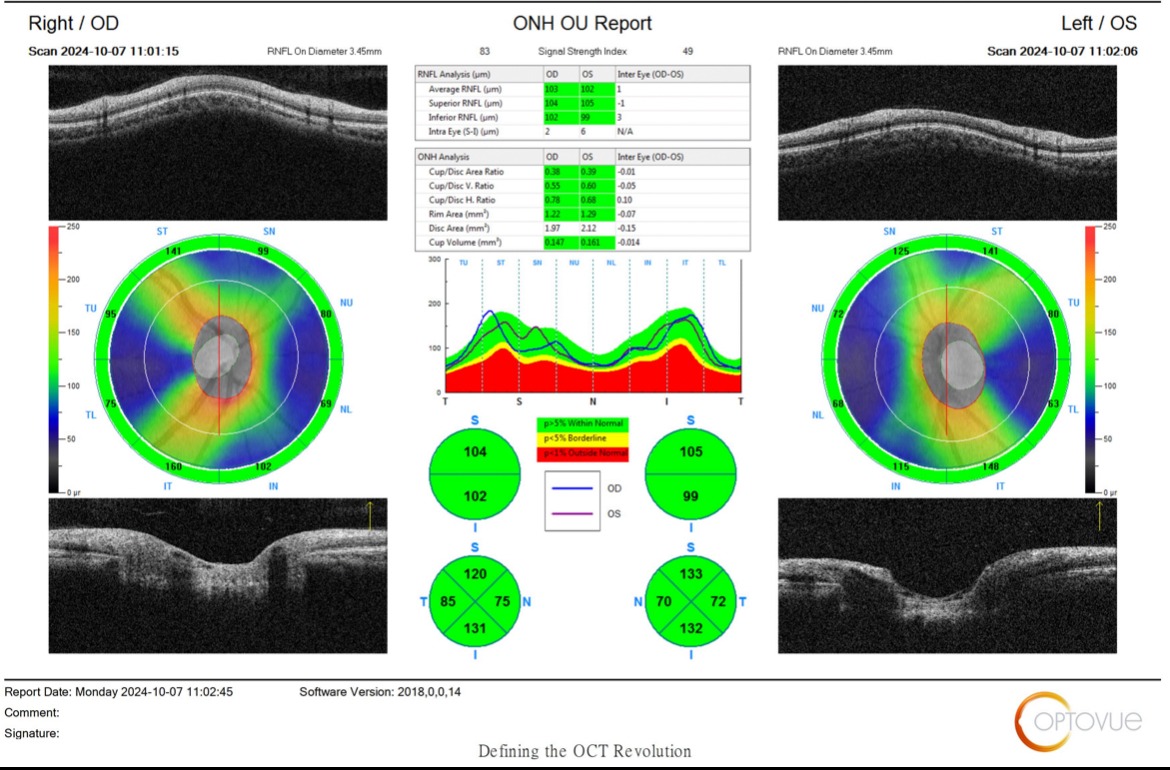

本人今年28歲,三年前健檢就有被標註左眼眼壓超標24,那時候沒有很在意,今年健檢又被測出右眼眼壓24,兩眼眼壓都偏高19~25左右

健檢中心請我要去醫院追蹤有可能是青光眼,目前去做了三總的OCT檢查,還要視野檢查等等還沒做,但是排到好久以後,心裡越想越害怕,

想請版主及各位幫忙看看我的OCT報告是否有青光眼?謝謝!

OCT報告

視神經厚度很正常很厚,但杯盤比較大,接近邊緣值,加上眼壓較高,所以目前看起來是疑似,未來可能是也可能不是,目前判斷不出來,所以要定期檢查,一年或半年去檢查一次就可以了

另外你視野一定正常,不用擔心